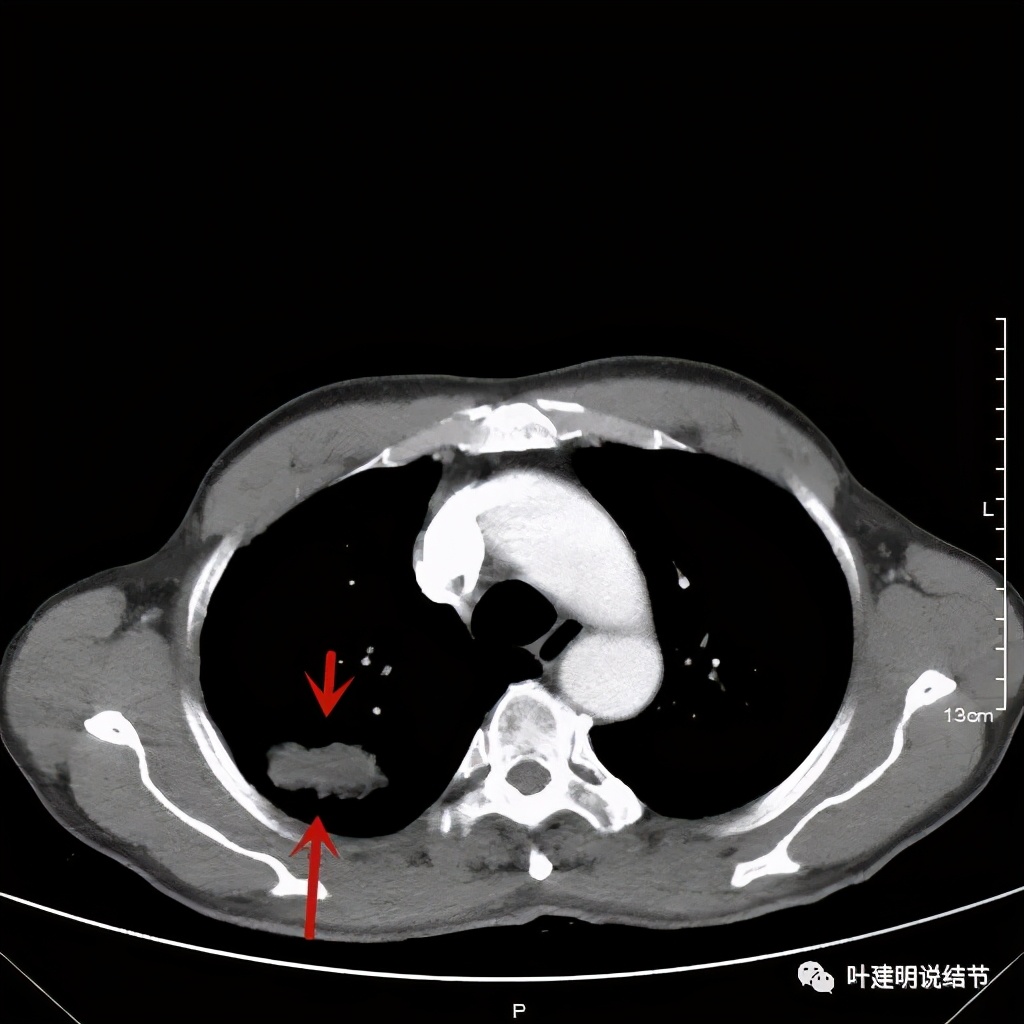

金华的某A,今年66岁,前几天在当地医院查胸部CT平扫发现右上肺占位,当时来找我看时,我想首先肺内占位是要警惕肺癌的,建议其住院进一步做增强CT,以及完善其他相关检查。其中增强CT报告示:右上叶约7*6厘米的肿块,增强后显著强化。而且某A曾于2018年5月在本院做过肺部CT,当时右上肺没有病灶的。我们先来看这次的CT图像:

红色示病灶,绿色示病灶旁边有磨玻璃成分,但较为模糊;蓝色箭头示病灶与胸膜间有牵拉,但力度不太够。

以上诸图是纵隔窗

总体上感觉,病灶比较大,不规则,不是圆形或圆形生长,周围有模糊磨玻璃影(考虑炎性渗出性?),虽有胸膜牵拉,但力度不够;增强有显著强化。病灶明显却无明显临床症状,普通感染是不像的,要么是结核,要么是肺癌。但肺癌的话,在2年前没有,2年内长到这么大,恶性程度应该很高,但其纵隔淋巴结却没有明显肿大。而且病灶的边缘部分过于光滑,没有见到肿瘤的细毛刺,膨胀性也不够。整体看病灶有点像“腰子”形,弯弯曲曲的。所以我的感觉更倾向结核性。查了肿瘤筛查指标如下: